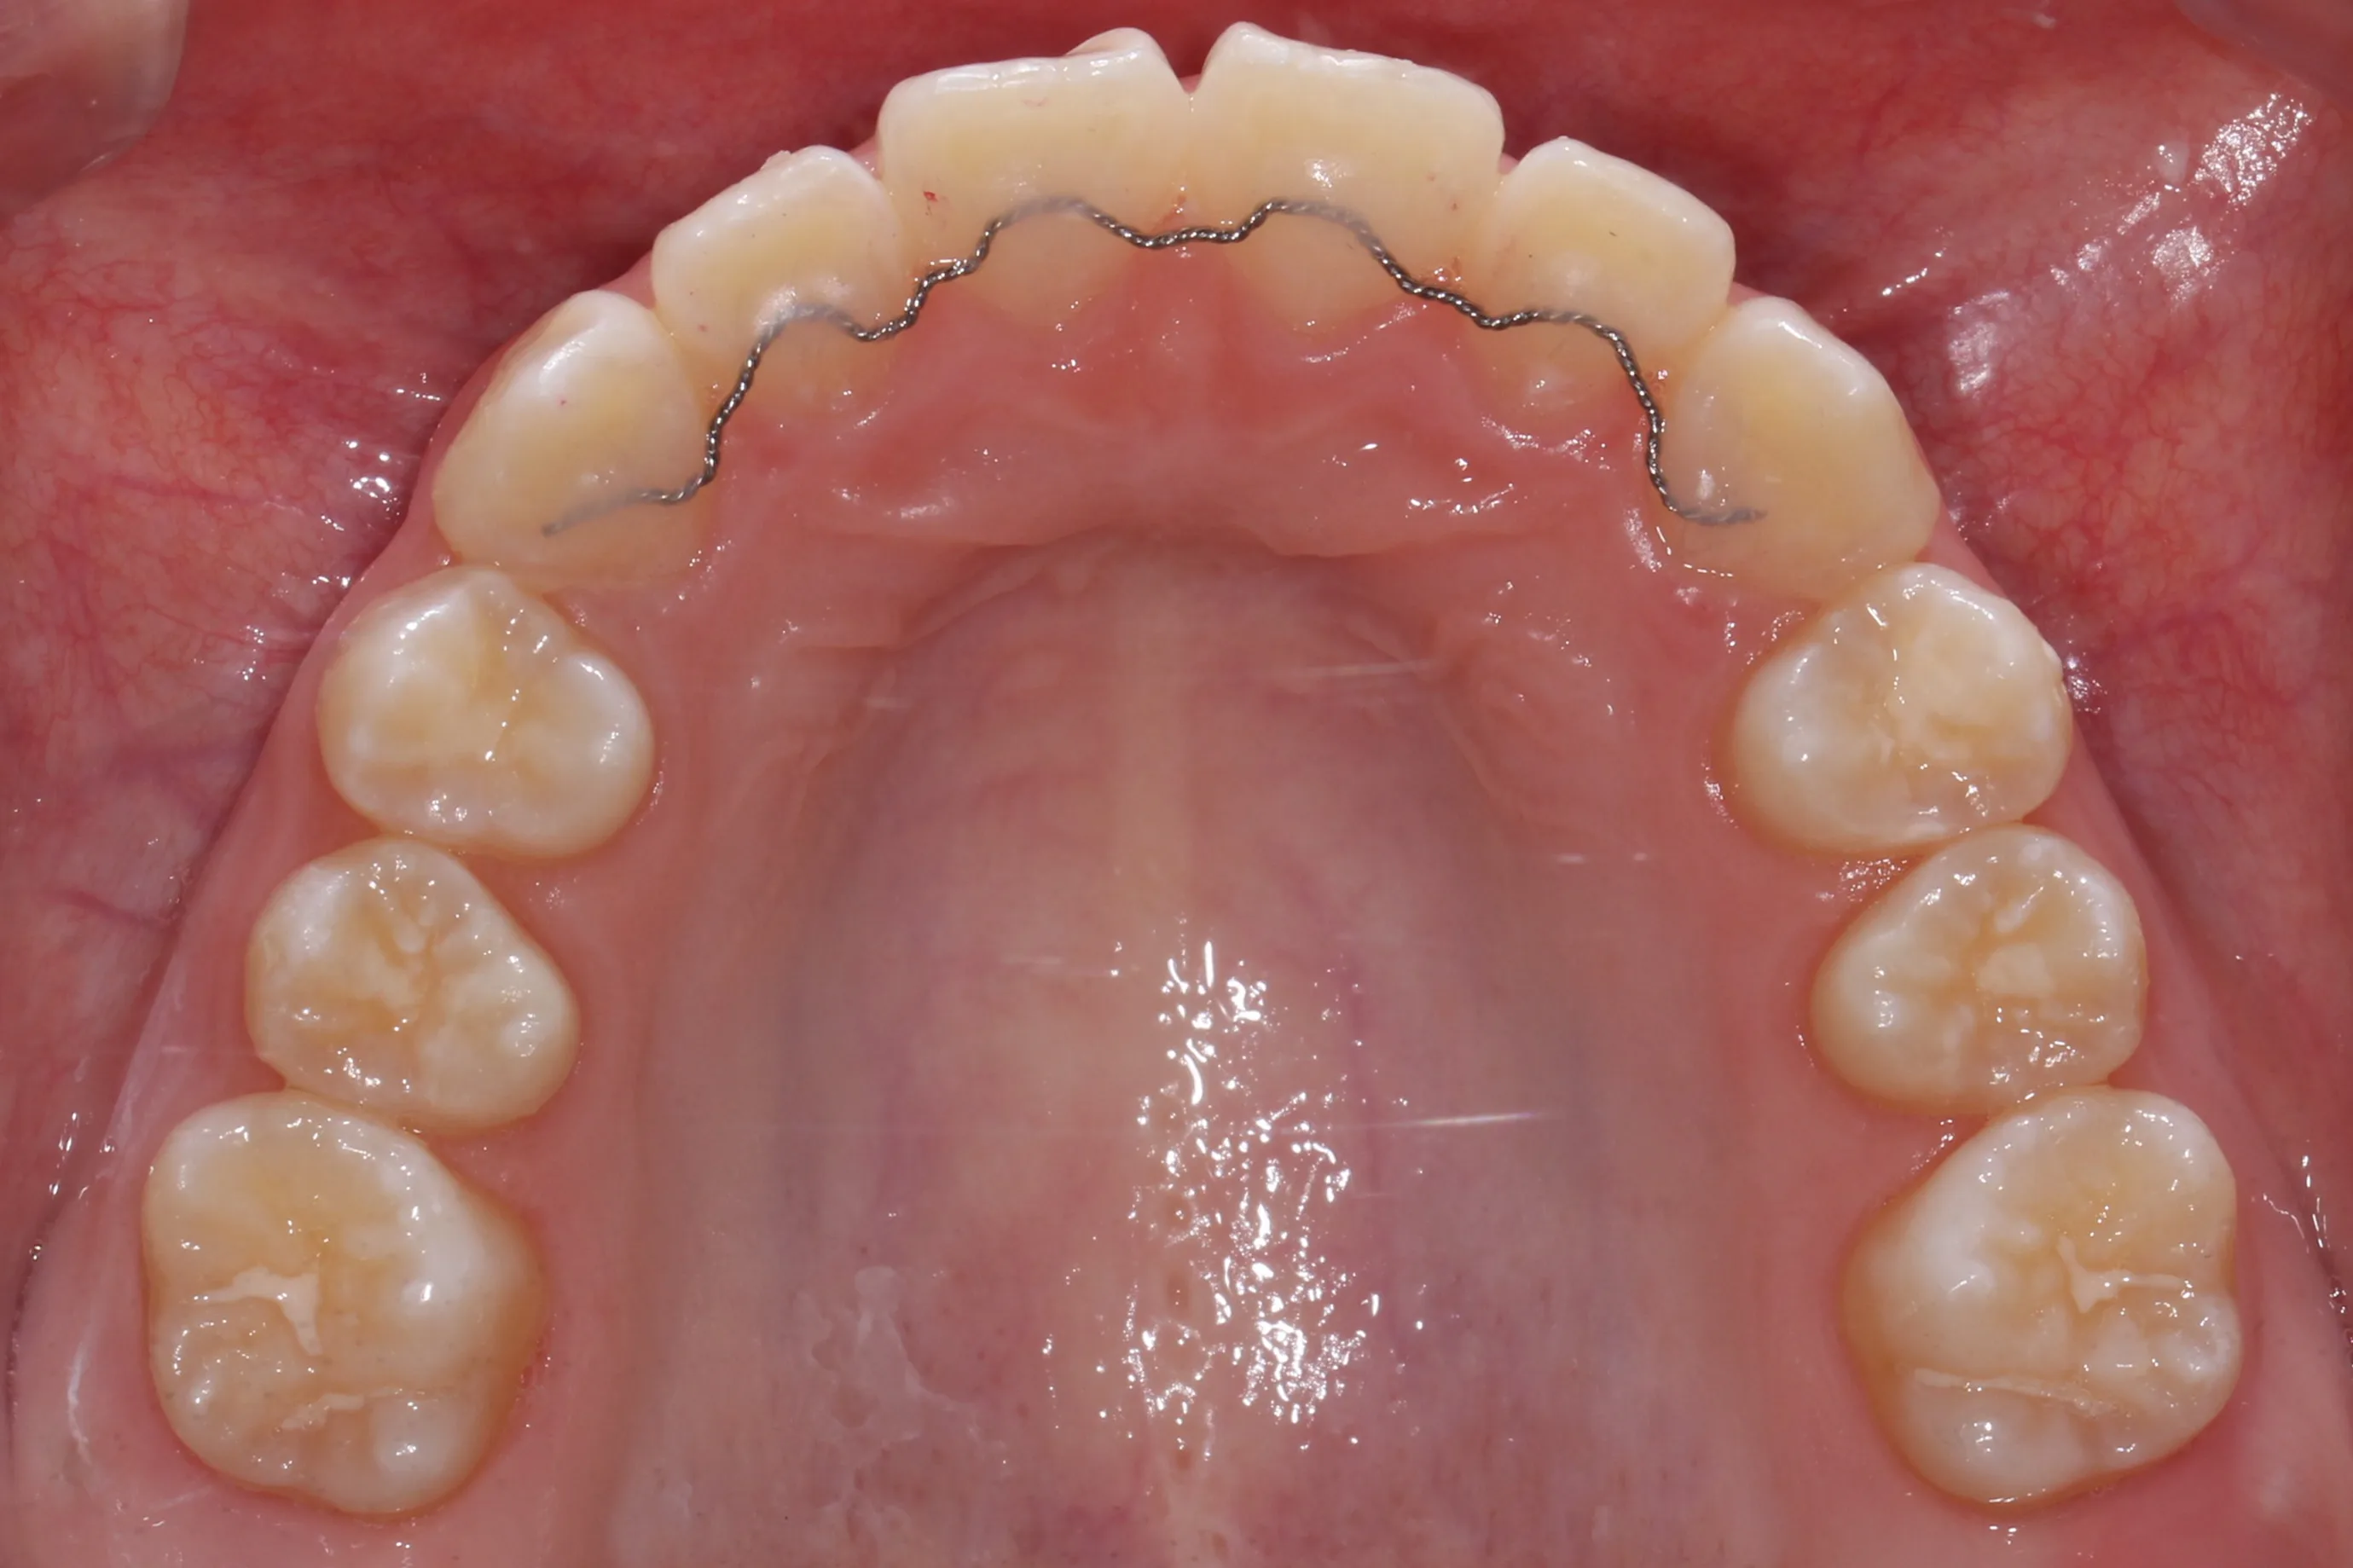

2년 7개월의 치료 과정을 거치며 환자분의 협조도 덕분에 안모 프로파일과 교합이 안정적으로 개선되었습니다. 성장기라고 해서 무조건 교정이 어려운 것은 아닙니다. 적절한 시기에 맞춤형 장치를 선택한다면 골격적 불균형을 효과적으로 바로잡을 수 있습니다.